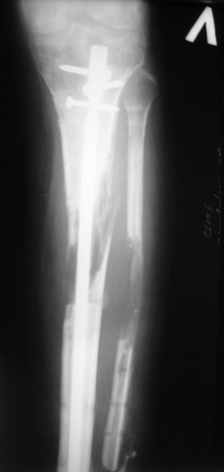

Ерсин, мы тоже имеем опыт такой фиксации. Подобную операцию за последние 3 года мы сделали трем пациентам. Снимки одного из них я прилагаю. К сожалению, ни в одном из этих 3-х случаев мы не получили удовлетворяющего нас результата. Очень трудно провести штифт, введенный антеградно ровно по центру таранной кости. Отсутствие подвижности между диафизом и дистальным отломком большеберцовой кости (после фиксации в аппарате в течение 1-2 мес) очень усложняет проведение штифта в центр блока таранной кости. Поэтому мы от этого пока отказались, и проводим штифт через пятку. При данном варианте фиксации подобных проблем не возникало ни разу.

Вложение не в текстовом формате было извлечено…

Имя     : 3.jpg

Тип     : image/jpeg

Размер  : 16031 байтов

Описание: отсутствует

Url     : http://weborto.net:8080/pipermail/ortho/attachments/20081209/5d3bc875/attachment-0006.jpg